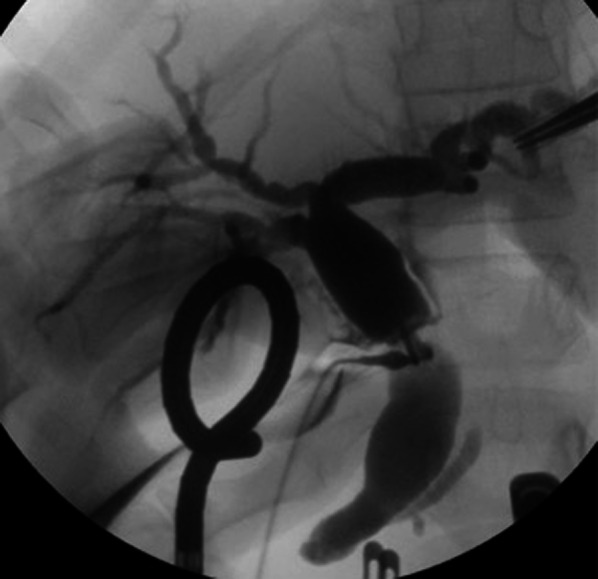

A 9-year-old girl was referred to our hospital for further examination regarding dilatation of the common bile duct, which was found by abdominal ultrasonography performed for the evaluation of elevated liver enzyme levels. Magnetic resonance cholangiopancreatography (MRCP) revealed dilated bile ducts from the left and right intrahepatic bile ducts to the common bile duct, and the patient was diagnosed with Todani type IV-A CBD (Fig. 1). The gallbladder was not detectable by abdominal ultrasonography, computerized tomography or MRCP; therefore, we suspected gallbladder agenesis preoperatively. The patient underwent laparoscopic excision of the extrahepatic bile duct to treat the CBD. Initial laparoscopic exploration did not reveal a gallbladder or cystic duct on the liver undersurface. Therefore, we considered gallbladder agenesis based on both preoperative imaging and intraoperative findings. Intraoperative cholangiography was performed by direct puncture of the common bile duct, and it did not show the gallbladder and bile duct (Fig. 2). However, during dissection of the hepatic hilum, we detected a cystic structure on the ventral side of the common hepatic duct, slightly to the right, and the presence of a small additional duct that originated from the cystic structure (Fig. 3). The size of the cystic structure was estimated to be 3 cm and the distance between the cystic duct and bifurcation was estimated to be 1.5 cm. A small amount of bile was drained upon incising the small duct. Thus, we diagnosed the cystic structure as an ectopic gallbladder with hypoplasia. After the ectopic gallbladder was removed, an excision of the extrahepatic bile duct followed by laparoscopic Roux-en-Y hepaticojejunostomy was completed without any complications. Postoperative histopathological evaluations of the resected specimen revealed Rokitansky–Aschoff sinuses in the resected cystic lesion (Fig. 4). Findings from the pathological investigations confirmed the diagnosis of an ectopic gallbladder. The patient’s postoperative course was uneventful, and she was discharged on the ninth postoperative day. She recovered without any hepatobiliary complication 10 months after the operation.